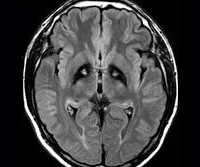

G23.0 Hallervorden-Spatz disease